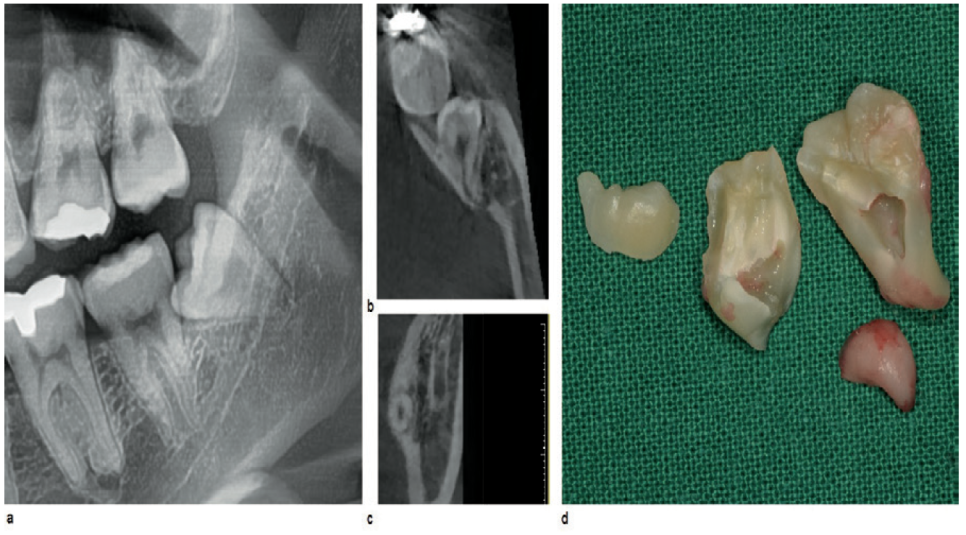

케이스 소개

파노라마 (a)

제3대구치의 뿌리 부분이 신경과 겹쳐 보이고

끝 부분에서 어두운 영역을 발견

CT (b,c)

치근 방향이 이미 설측 피질골과 닿아 있는 상황

이대로 발거를 할 경우

뼈가 파손될 가능성이 있음